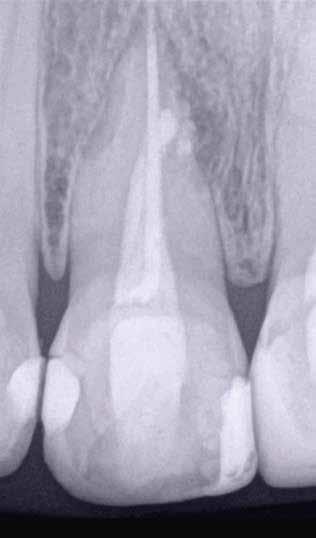

Egy 63 éves páciens korábban már kezelt bal alsó első nagyőrlőfogából (3.6) eredő mérsékelt fájdalom miatt kereste fel rendelőnket. A kórtörténetében panasza szempontjából releváns információ nem szerepelt. Az elkészült CBCT-felvételen a korábbi kezelések során észre nem vett, jelenleg feltáratlan meziobuccalis csatornát, valamint a mezialis és distalis gyökerek körül kialakult periapicalis elváltozást, és ezt a léziót borító intakt buccalis corticalis csontlemezt láttunk.

Klinikai vizsgálat során vertikális kopogtatási érzékenységet jelzett. A fog körül mérhető szondázási mélység és a fogmobilitás fiziológiás volt. A CBCT-felvételen nem észleltünk a csontos regeneráció megindulására utaló jeleket (1. a–c. ábrák). A korábban gyökérkezelt, gyökértömött és revideált 3.6-os fog esetében az alábbi diagnózis került felállításra: periodontitis periapicalis symptomatica. A panaszokat okozó fog további ellátása során navigált endodonciai mikrosebészetet kívántunk alkalmazni. Az alsó állcsontról intraorális szkent (TRIOS, 3Shape) készítettünk, és a felszíni topográfiát tartalmazó STL fájlt, valamint a CBCT-felvétel készítése során nyert DICOM fájlokat a Blue Sky Bio szoftver segítségével egyesítettük. A sebészi sablon megtervezésére az így kapott háromdimenziós képet használtuk. A sablon kialakítása során arra törekedtünk, hogy a sablon egyértelműen meghatározza a gyökércsúcsi terület eléréséhez szükséges csontablak határait (1. d. ábra)